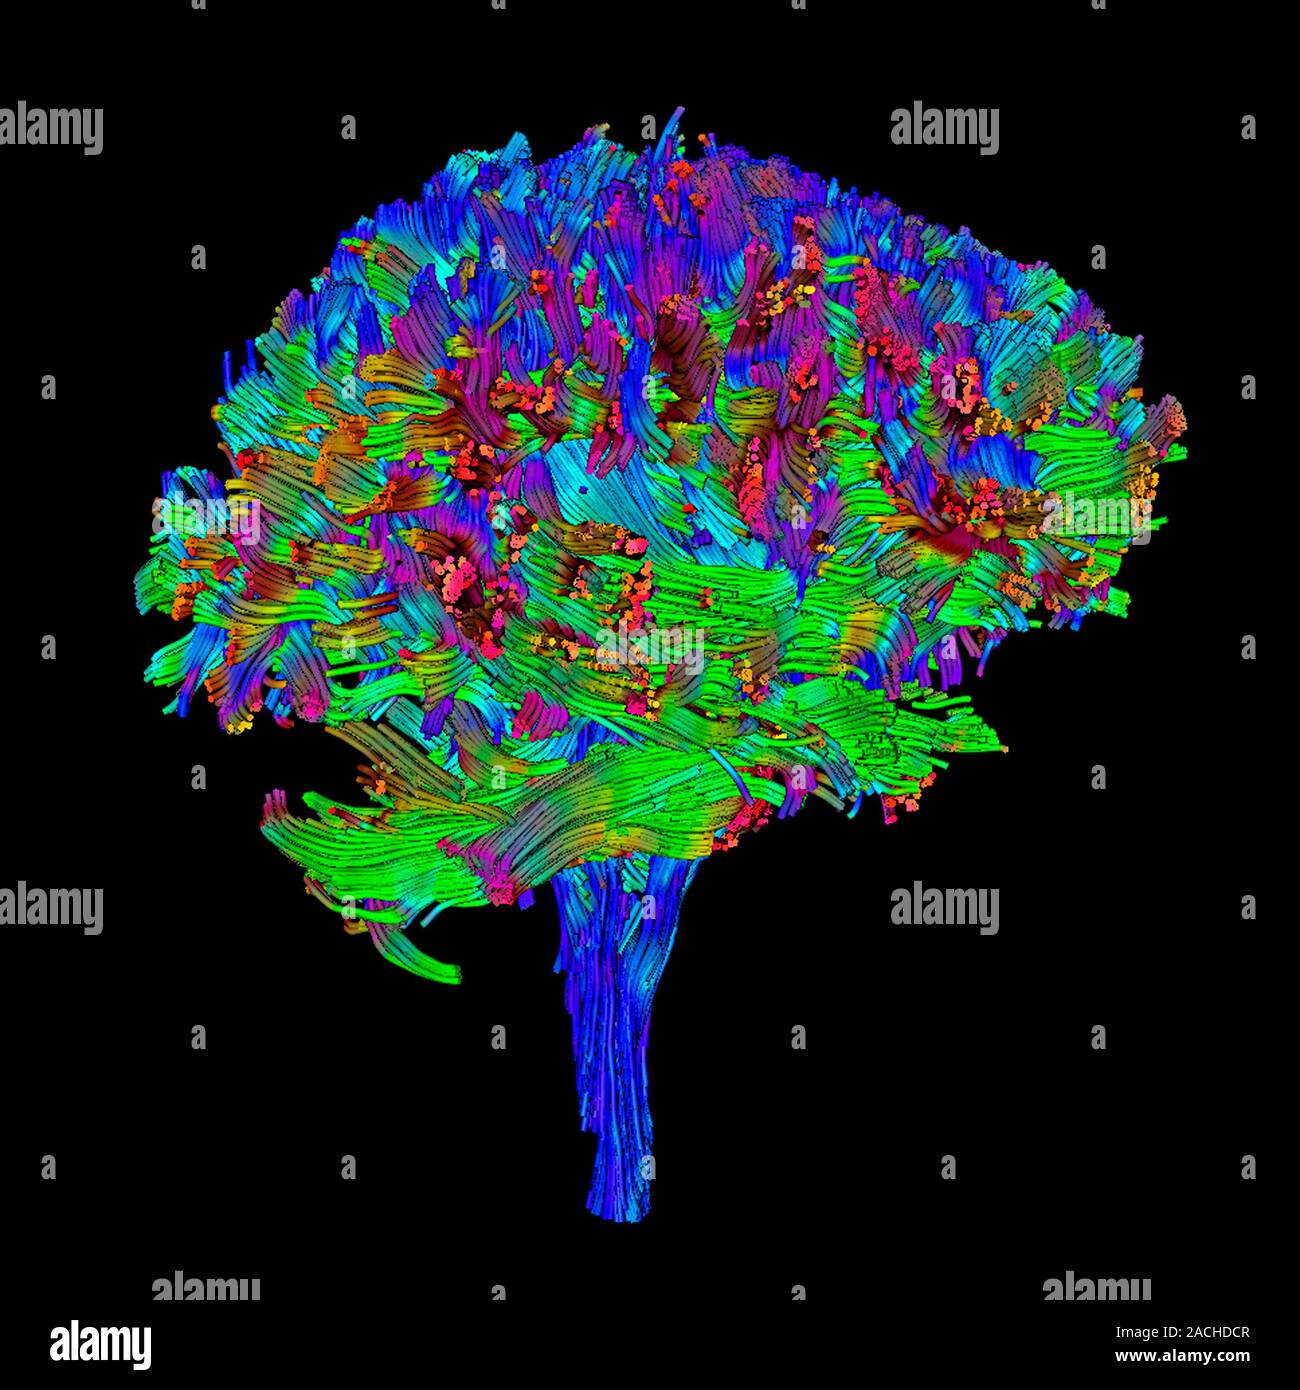

Diffusion tensor